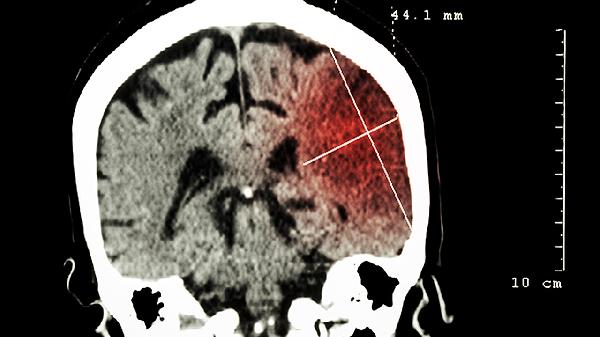

3、影像学表现

CT检查显示脑挫伤为局部低密度影,周围可有水肿带。脑裂伤则可见脑组织断裂线状影,可能伴有颅内积气或异物影。